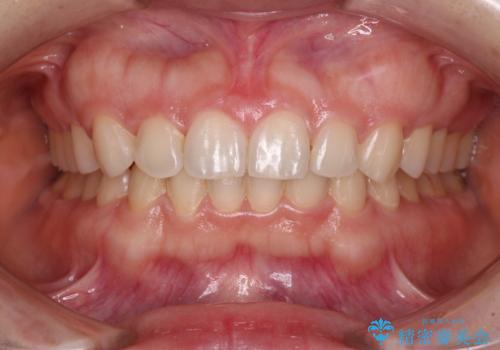

- 前歯のデコボコを治したいとのことで来院された患者様です。

上下顎ともに歯列全体の後方移動とIPR(歯と歯の間を削る)によってデコボコが解消するように設計し、インビザラインにより治療を行うこととしました。

下顎前歯は後戻りを起こしやすいため、舌側を細いワイヤーで固定し、マウスピース型リテーナーで保定を行うこととしました。